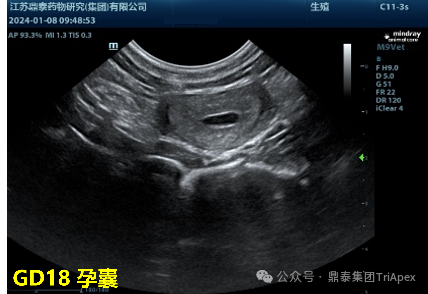

◆ 确定妊娠状态

在交配后,最早可在妊娠第18天(GD18)[2]通过B超检查确认胚胎是否着床,从而判断妊娠是否成功;同时,B 超检查还可明确胚胎的着床位置,判断是否为宫内妊娠或宫外妊娠等情况。该项检查为后续试验的顺利开展提供了基础保障。